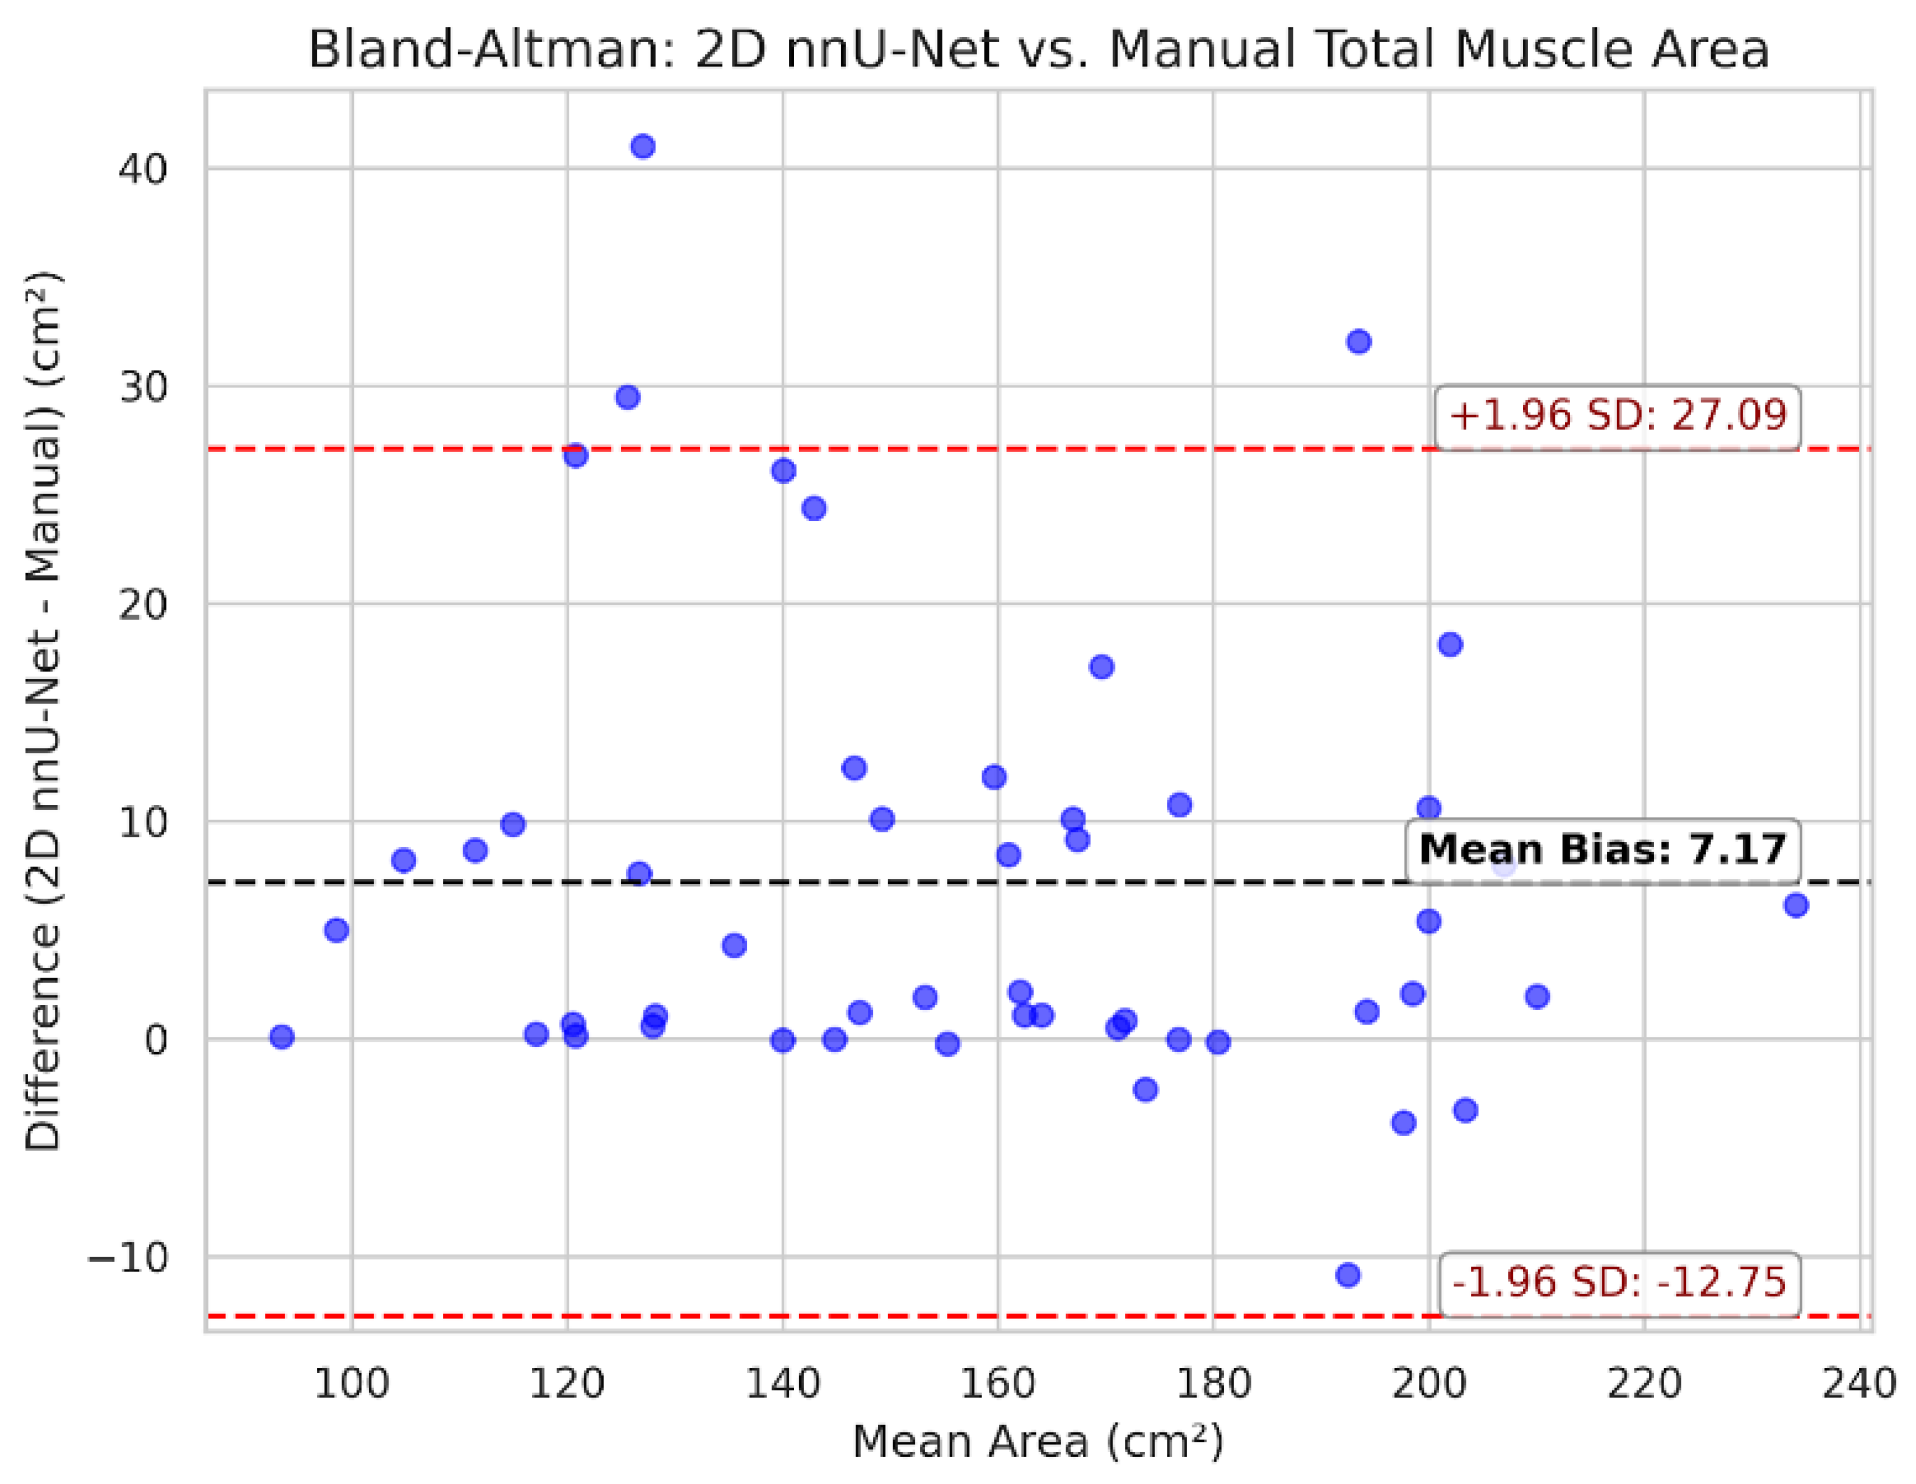

3.3. Clinical Agreement and Bias Analysis

| Metric | Pearson r | MAE | Mean bias (nnU-Net - manual) |

|---|---|---|---|

| Total muscle area (cm²) | 0.955 | 8.00 | +7.17 |

| Total mean attenuation (HU) | 0.968 | 2.33 | -1.67 |